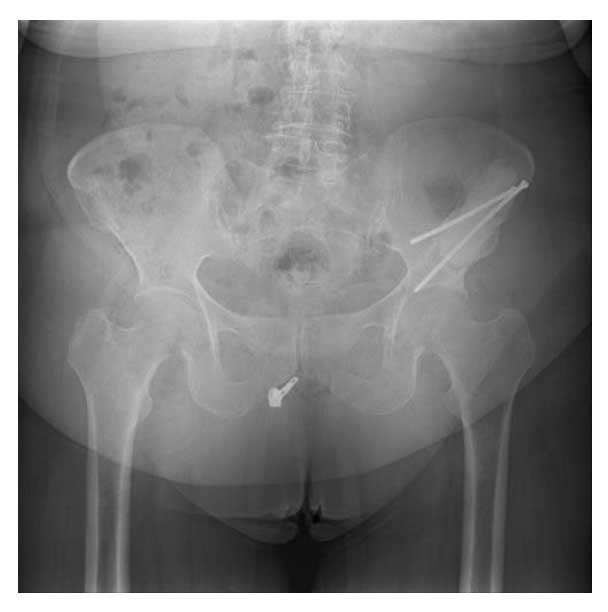

Ameliyat Sonrası: Röntgende tümör temizlendikten sonra oluşan boşluğun kemik çimentosu ile doldurulması ve iki adet uzun vida ile güçlendirilmesi görülmekte.